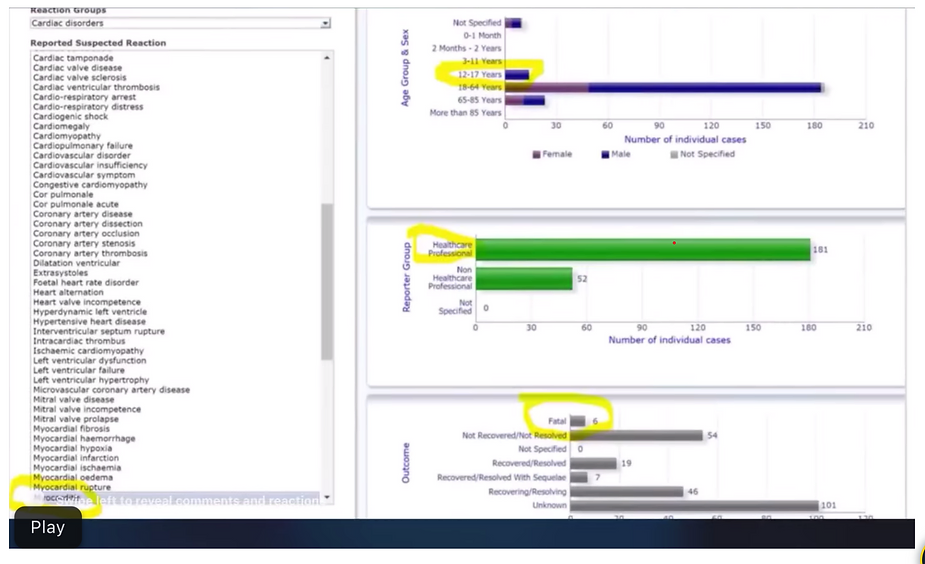

As the UK statics are showing now, the majority dying from the Vax are those that have been triple injected with the gene altering graphene, ferritin, luciferase, PEG and parasitical toxic with the Trypanosoma parasite causing myocardititis all in the so-called CoVid – 19 vaccine serum.

Table 12, found on page 43 of the latest report shows the number of Covid-19 deaths by vaccination status in England between the 24th of January and the 20th of February, 2022, and it confirms yet again that the vast majority were recorded among the triple vaccinated population.

Source –

In all, there were 4,861 Covid-19 deaths between 24th of January and the 20th of February, 2022, and the triple vaccinated population accounted for 3,120 deaths. Whilst the nonvaccinated population accounted for just 559 deaths.

Overall, the vaccinated population accounted for 89% of all Covid-19 deaths during these four weeks, with 4,302 recorded deaths. This means the vaccinated population now account for 9 in every 10 deaths, and the triple vaccinated population account for 4 in every 5 deaths.

But what’s most important here is that things are improving by the week for the nonvaccinated population, whilst they take a turn for the worse by being intentionally exposed to elevated microwave radiation or the triple vaccinated population starts dying off from accumulated graphene and ferritin oxide poisoning amplified by 5G pulsating microwave radiation causing cell membrane degeneration, pathological coagulating leading to blood clots, oxygen deprivation and then death by suffocation!